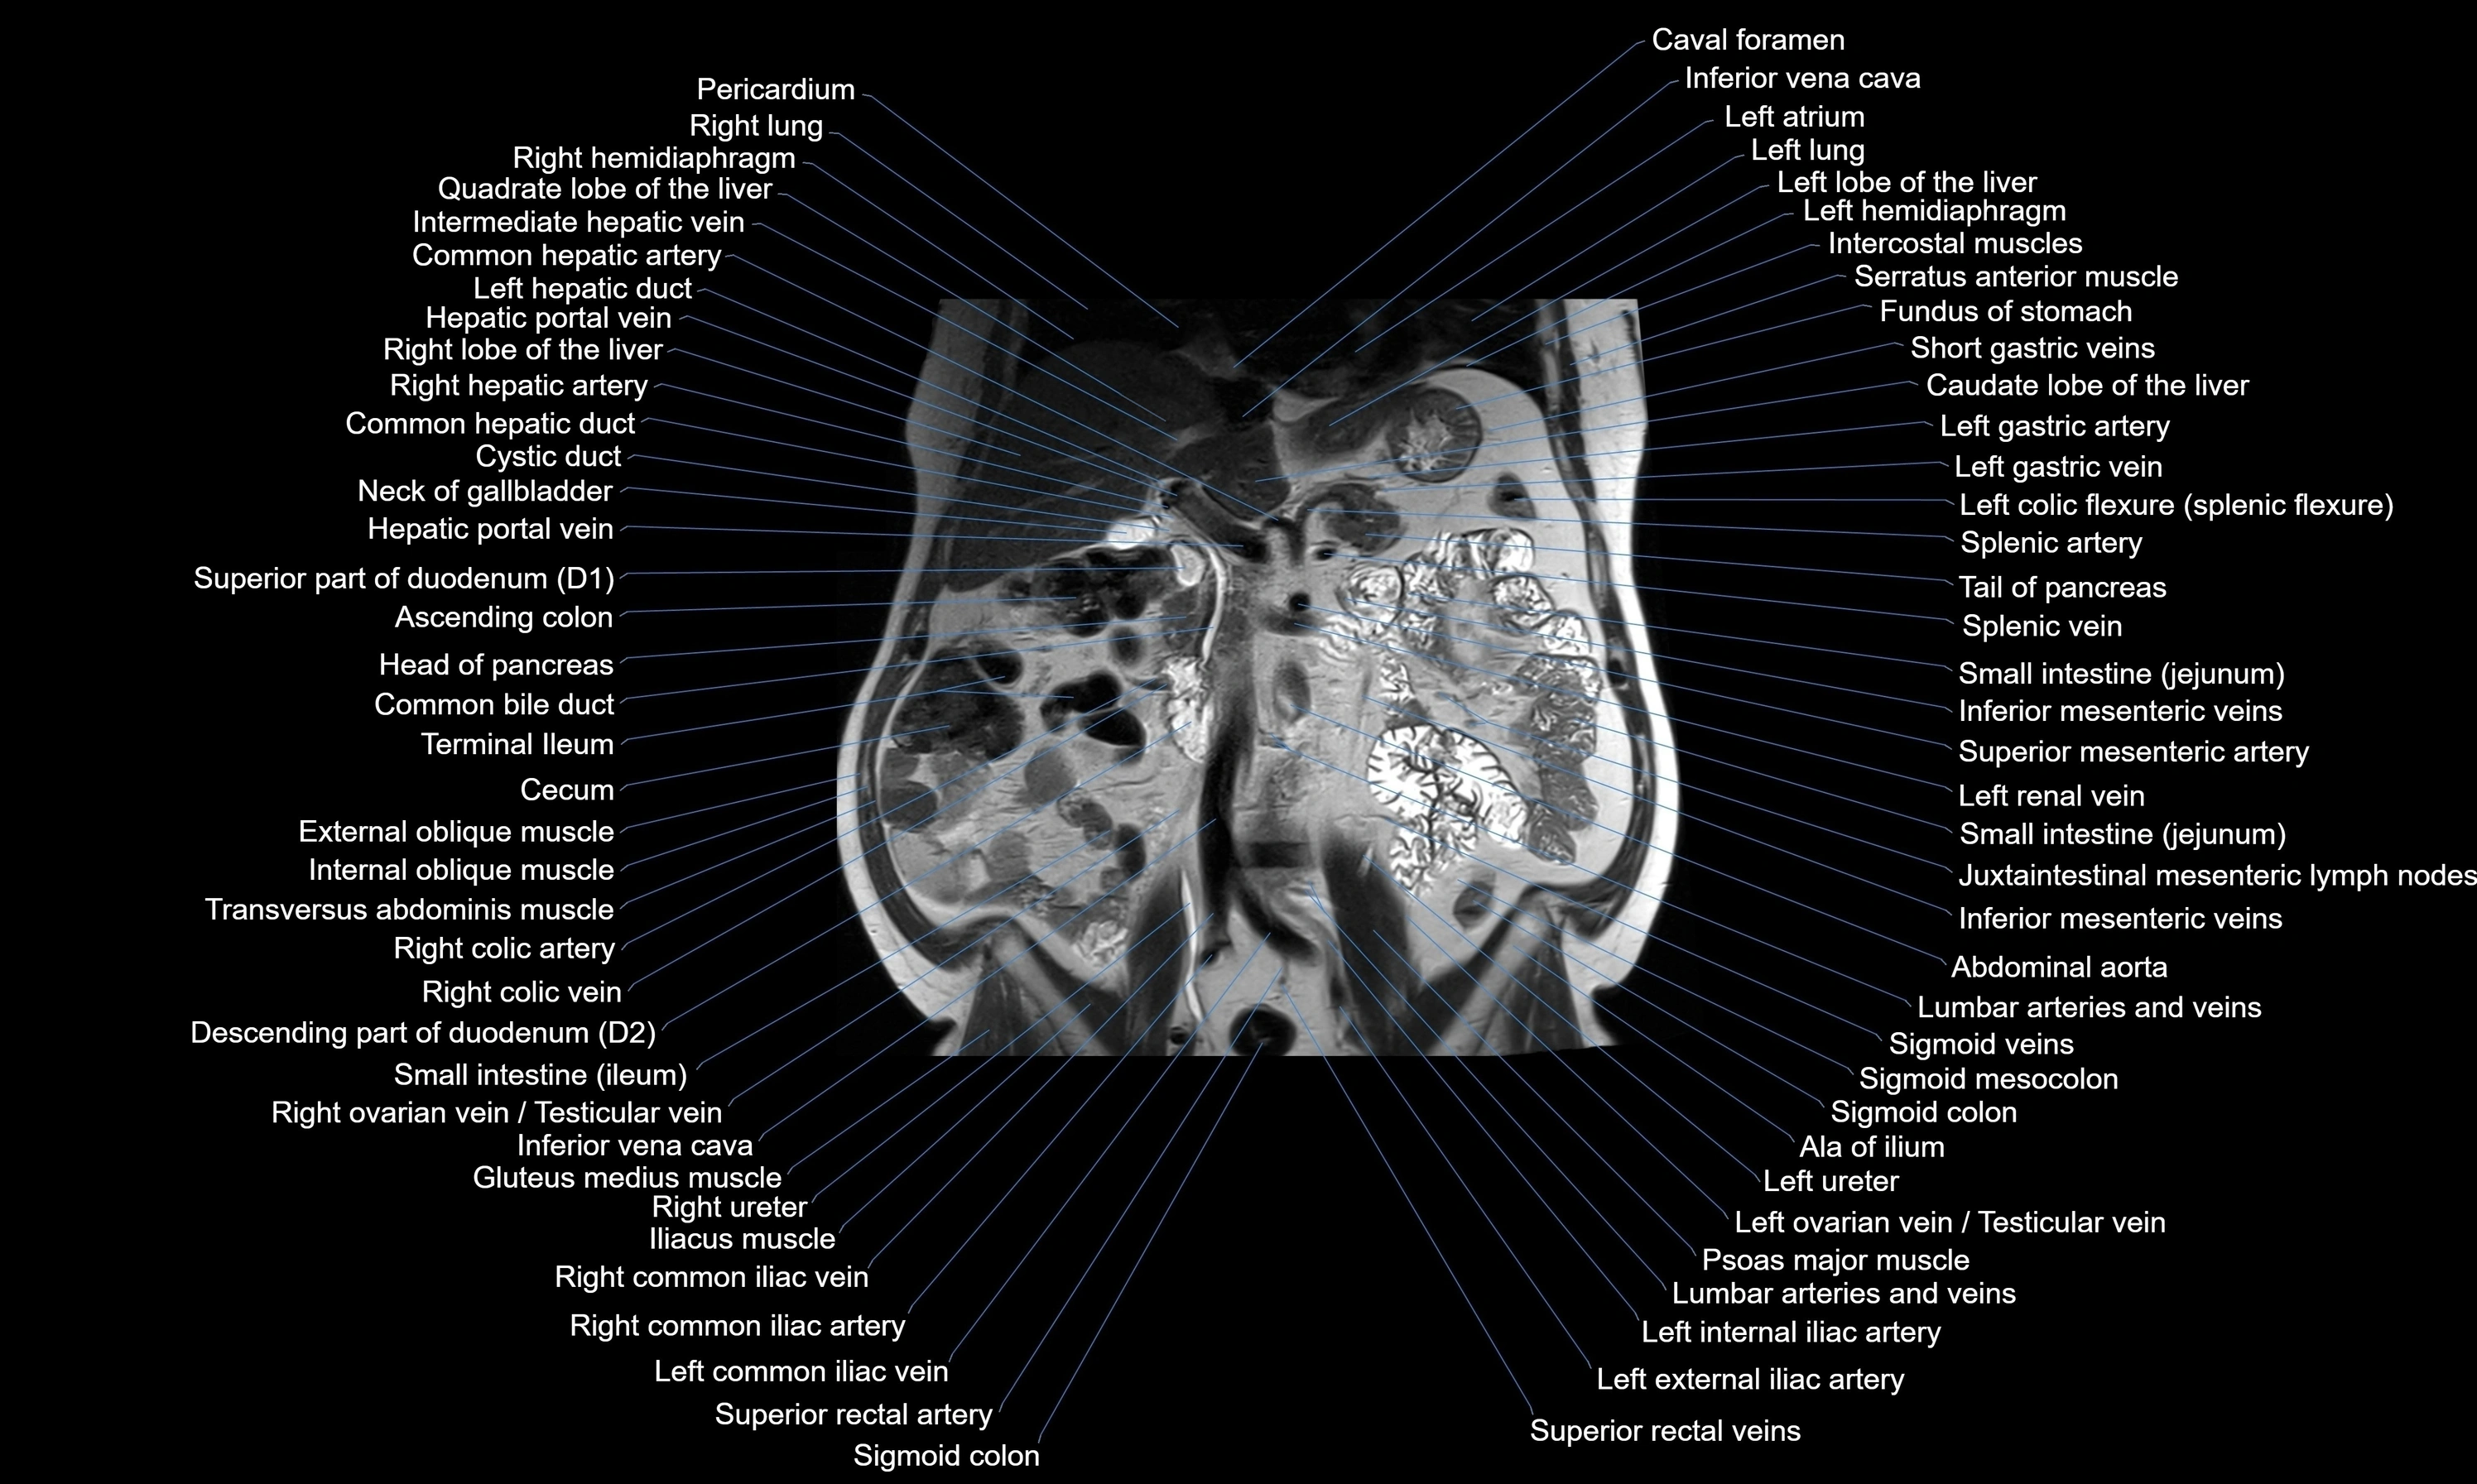

MRI images